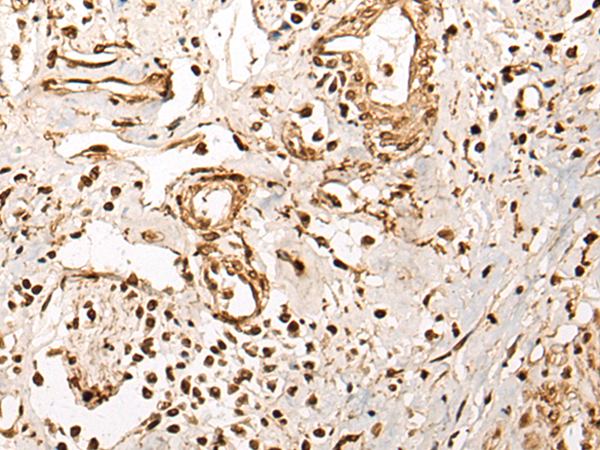

分类: 科研抗体货号: P02459别名: CDFE; NRXN4; AUTS15; CASPR2; PTHSL1应用: WB,IHC反应种属: Human, Mouse, Rat